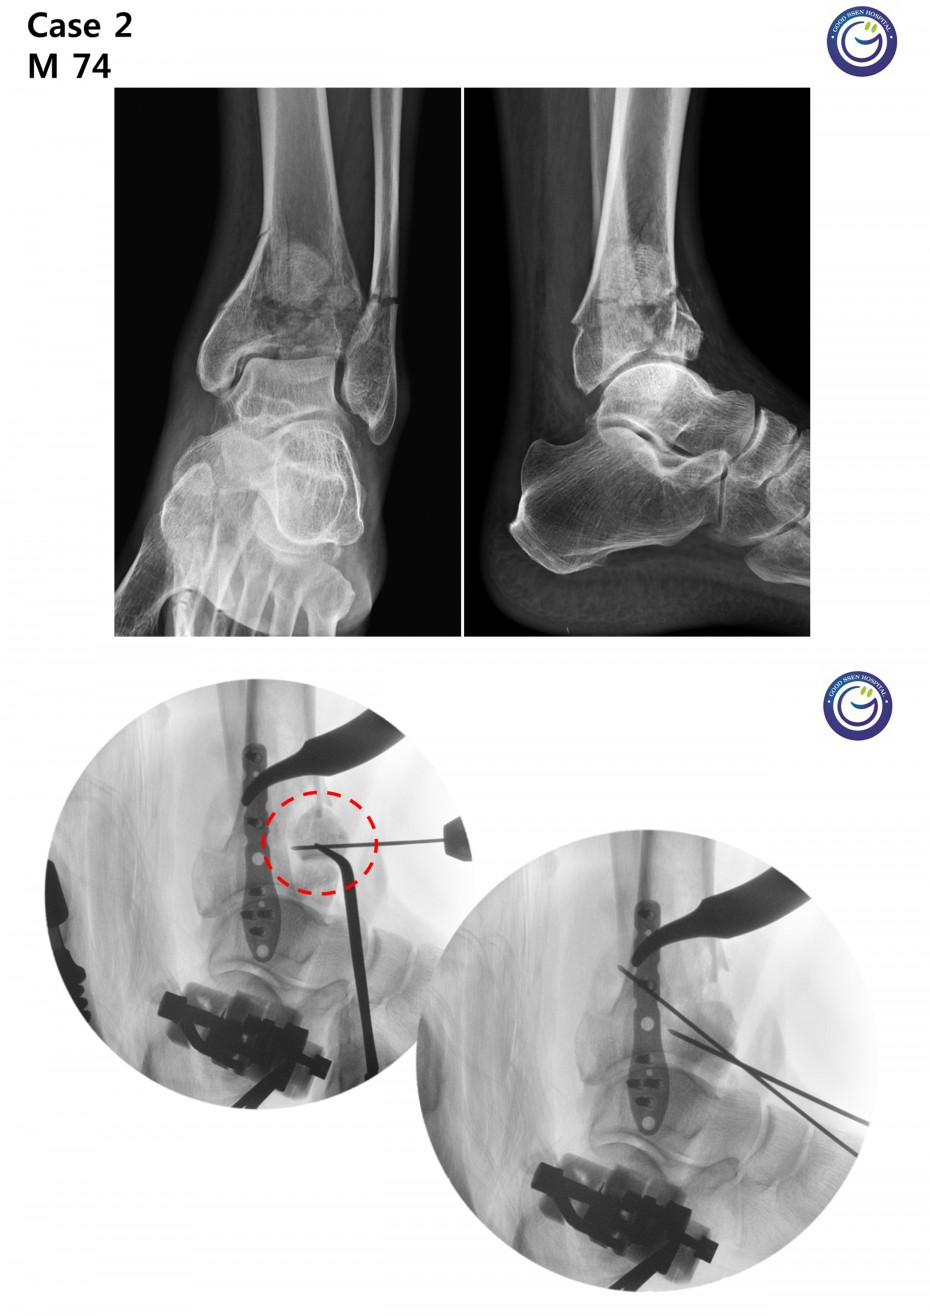

관절을 침범하는 심한 분쇄골절

절개없이 고정하는 최소침습적 고정방법 (MIPO)